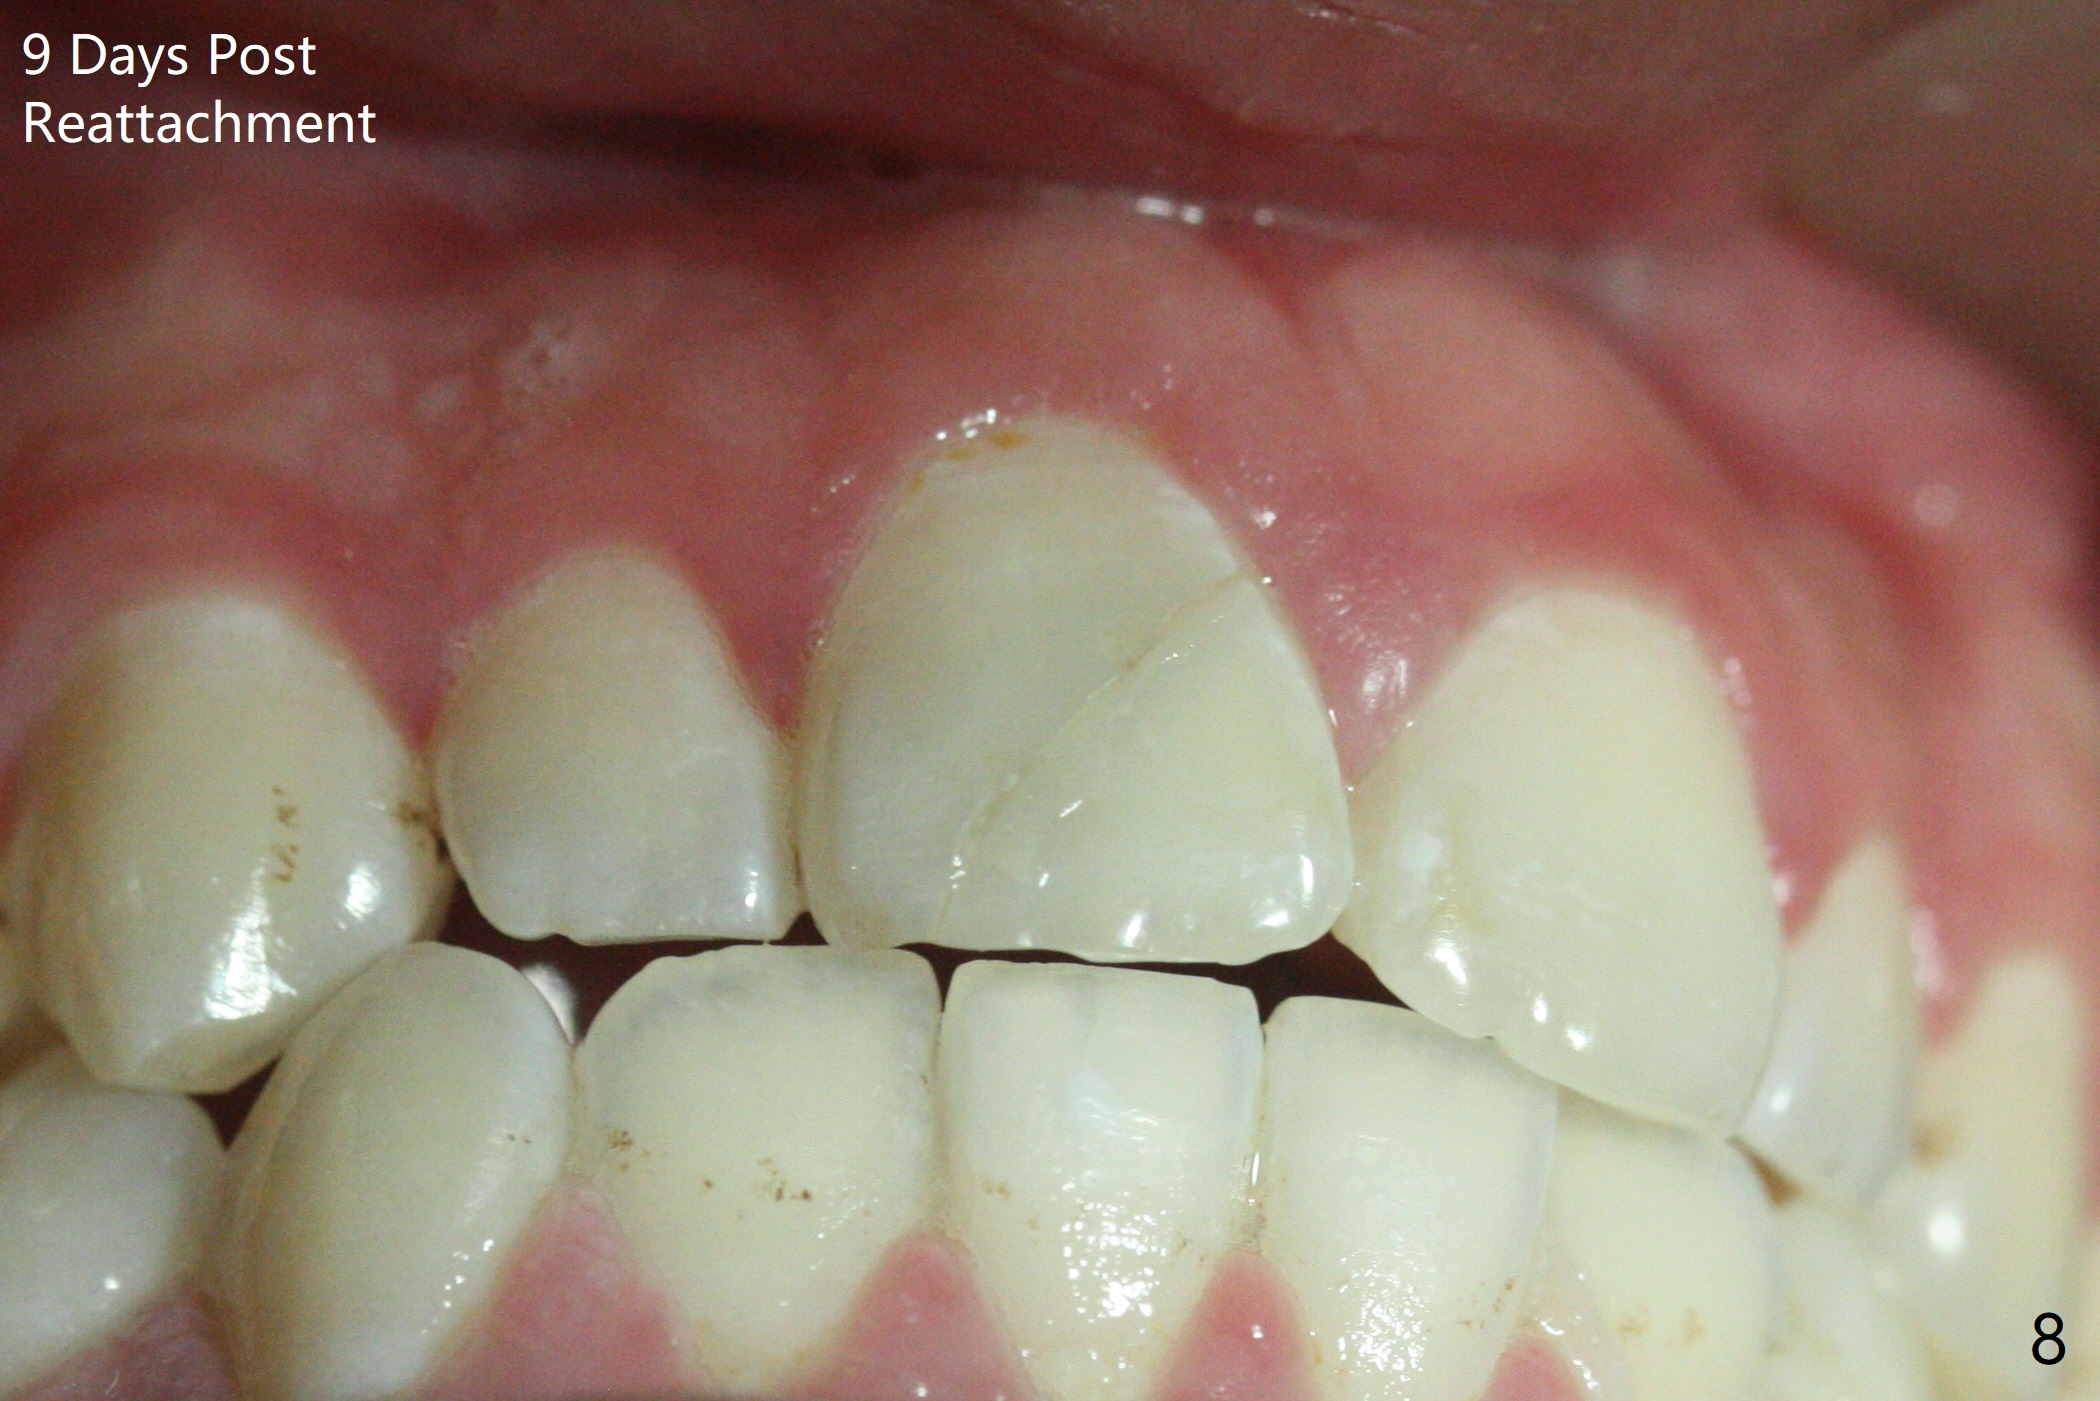

A 16-year-old man fractured the tooth #8 yesterday (Fig.1) with pulpal exposure (Fig.2) and slightly subgingival (Fig.3 <). With 2 gingival retraction cords, rubber dam and floss, the mesial margin is exposed (Fig.4). The mesial pulpal horn is increased slightly with a 330 bur with minimal pulpotomy. MTA is applied (Fig.5 <). A curette is placed over the MTA for hemostasis while it is setting. RelyX Ultimate Adhesive Resin Cement bonding is used to reattach the fracture fragment in place (Fig.6,7). Pulpal vitality will be monitored. A crown will be placed if the tooth discolors due to MTA and the pulp remains vital. Mineral trioxide aggregate (MTA), composed mainly of tricalcic silicate, tricalcic alluminate, bismuth oxide, is a particular endodontic cement. It is made of hydrophilic fine particles that harden in the presence of dampness or blood. The re-attached tooth remains asymptomatic 9 days postop (Fig.8) when he returns for prophy.

16岁男孩,昨天右上中切牙撞击电脑发生折裂(图一),近中牙髓角暴露(图二),裂缘稍微龈下(图三 <),使用两个牙龈牵拉线,橡皮障和牙线,近中折裂边缘暴露(图四)。你会如何处理?使用330钻头稍微扩大髓角开口,去除少量牙髓,填入微量MTA (图五<),希望形成新的牙本质,关闭开口,维持牙髓活性。出血控制后,应用树脂粘合剂将断片固定于原位(图五,六,七)。术后9天牙齿无症状(图八),病人回来洗牙。